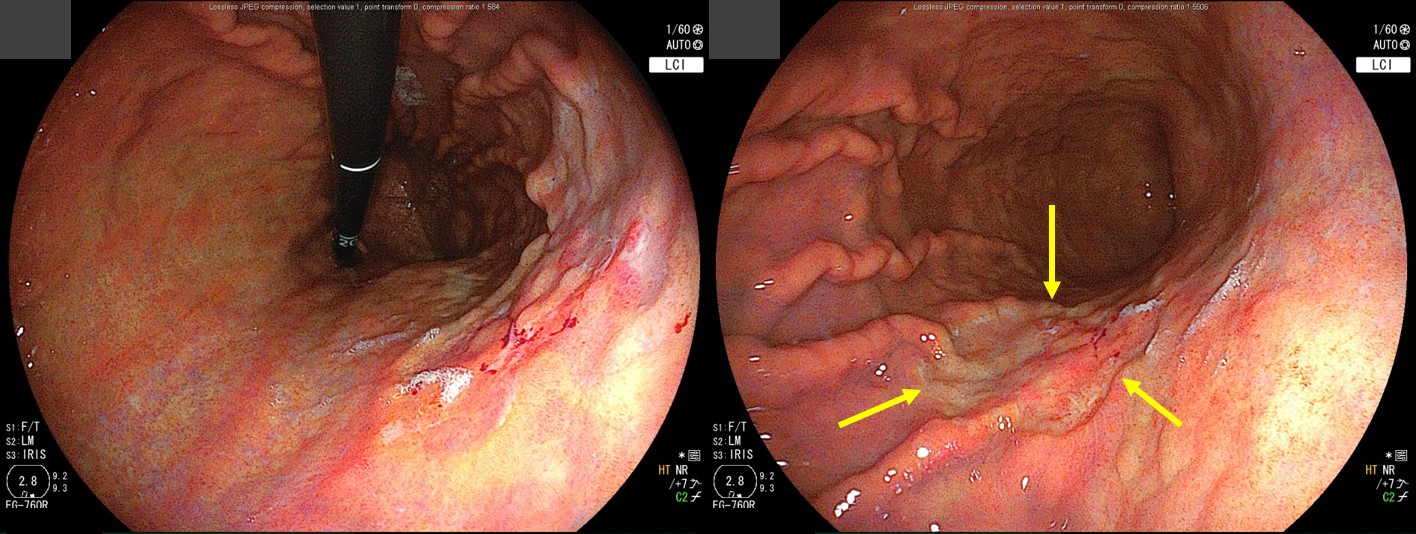

A depressed type of EGC was found. What is your treatment option?

We decided to try a less-invasive surgery, the pylorus preserving gastrectomy. Preoperative clipping was done.